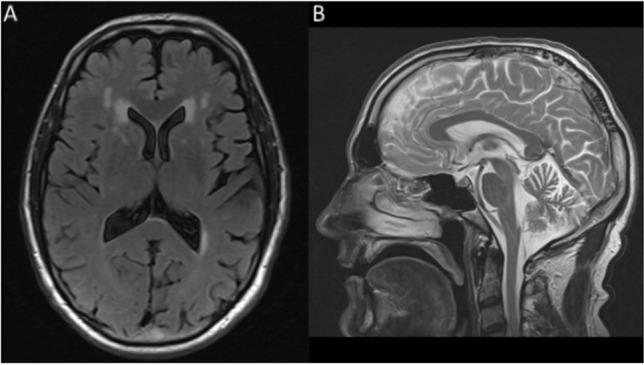

Inherited prion diseases (IPDs) are phenotypically diverse neurodegenerative conditions caused by mutations in the prion protein gene (PRNP). We describe IPD due to a novel PRNP E146G mutation in a 50-year-old man presenting with slowly progressive dysarthria, prominent myoclonus especially in the lower limbs, and less prominent gait ataxia, pyramidal and extrapyramidal signs. Cognitive impairment was not overt at disease onset. MRI revealed cerebellar atrophy and white matter hyperintensities. His 46-year-old sister carries the mutation and has subtle gait ataxia and dysarthria. Both patients exhibit a distinctive fluid biomarker profile: in CSF S100B is > twofold upper limit of normal, total tau is moderately elevated, and neurofilament light chain, 14-3-3 and RT-QuIC are negative; in plasma there is marked elevation of GFAP but repeatedly normal neurofilament light chain. The proband's father died aged 55 following an 8-year dementing illness with similar presentation. Post-mortem revealed cerebellar cortical atrophy and profuse large PrP amyloid plaques across cerebral and cerebellar grey matter. Immunoblotting identified low molecular weight protease-resistant PrP fragments. E146G mutation IPD broadly fits into the historical Gerstmann-Sträussler-Scheinker disease spectrum but, based on deep clinical phenotyping of this initial pedigree, we highlight some distinctive features, which may aid in identification of this disease.

遗传性朊病毒病(IPDs)是由朊病毒蛋白基因(PRNP)突变引起的表型多样的神经退行性疾病。我们描述了一名50岁男性因新的PRNP E146G突变导致的IPD,该患者表现为缓慢进展的构音障碍、明显的肌阵挛,尤其是下肢,步态共济失调、锥体束和锥体外系体征相对不明显。疾病发作时无明显认知障碍。MRI显示小脑萎缩和白质高信号。他46岁的妹妹携带该突变,有轻微的步态共济失调和构音障碍。两名患者均表现出独特的生物标志物特征:脑脊液中S100B高于正常上限两倍,总tau中度升高,神经丝轻链、14-3-3和实时QuIC检测均为阴性;血浆中GFAP明显升高,但神经丝轻链反复检测正常。先证者的父亲在患痴呆症8年后,于55岁去世,临床表现相似。尸检显示小脑皮质萎缩,大脑和小脑灰质有大量大的PrP淀粉样斑块。免疫印迹法鉴定出低分子量蛋白酶抗性PrP片段。E146G突变的IPD大致符合历史上的格斯特曼-施特劳斯勒-谢inker病谱系,但基于对这个初始家系的深入临床表型分析,我们突出了一些独特特征,这可能有助于识别这种疾病。